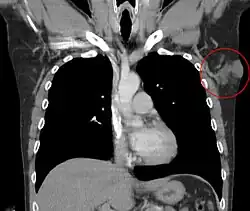

| Carcinoma basocelular ou basalioma | Possui translucência pérola, com minúsculos vasos sanguíneos na superfície e às vezes ulceração. O mais comum (75% dos casos) e menos agressivo. Quase sempre aparece no rosto, pescoço ou braços pois são áreas altamente expostas a luz solar. Os carcinomas basocelular são originários da epiderme e dos apêndices cutâneos acima da camada basal, como os pêlos, por exemplo. Possui altos índices de cura, principalmente devido à facilidade do diagnóstico precoce.[20] | |